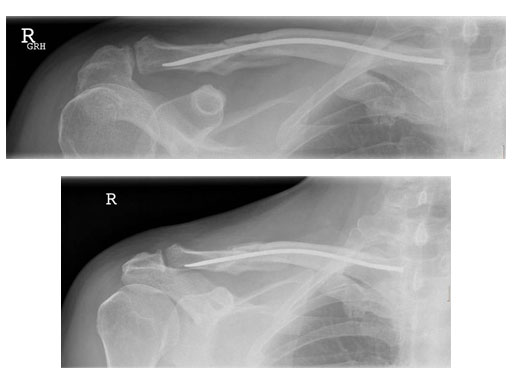

Case 1: Male, 56 years, Bicycle accident